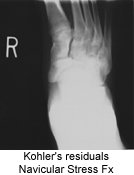

Koehler's Disease

Koehler's disease was thought by many to be avascular necrosis of the tarsal navicular primarily based on the radiographic signs. It is now a much more controversial subject. Kohler's disease is can be a very confusing and ambiguous entity due to uncertain etiology and often times vague symptoms. A history of trauma is only elicited in approximately 35% of cases and symptoms that correlate with the radiographic signs are very sporadic.

The radiographic appearance is sclerosis, overall flattening and deformity of the navicular. But, again, it's the associated signs and symptoms, as described that must be present for a confident diagnosis. MRI or bone scan may help confirm the diagnosis, but because of its self-limiting nature, it most likely is not warranted.